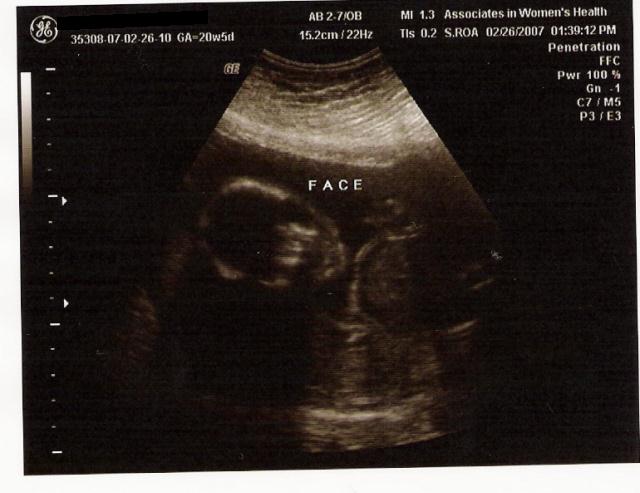

OMG! I can't believe it. I'm half way through this pregnancy! ANNNNNND....

IT'S A GIRL!!!

The pic is of her "face". Not that you can really see anything other than the skull...I so CAN NOT afford that 4D thing. Would be cool though. They're just damned expensive.

File Type: jpg girl2.jpg (49.2 KB, 327 views)